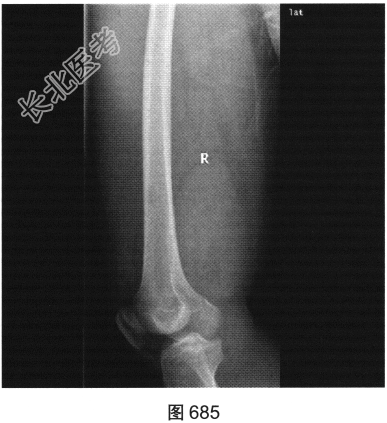

- 多项选择题2.[提示]患者X线检查见图684、图685。从以上X线平片中可以发现哪些异常表现( )

A、右股骨骨髓腔内未见明显异常密度影

B、右侧股骨形态可,可见骨质破坏

C、右大腿后方肌群软组织肿块边界清楚,密度均匀,未侵犯邻近骨质结构

D、右大腿后方肌群广泛水肿

E、右大腿后方肌群软组织肿胀,可见肿块影

F、右大腿软组织内密度不均匀增高